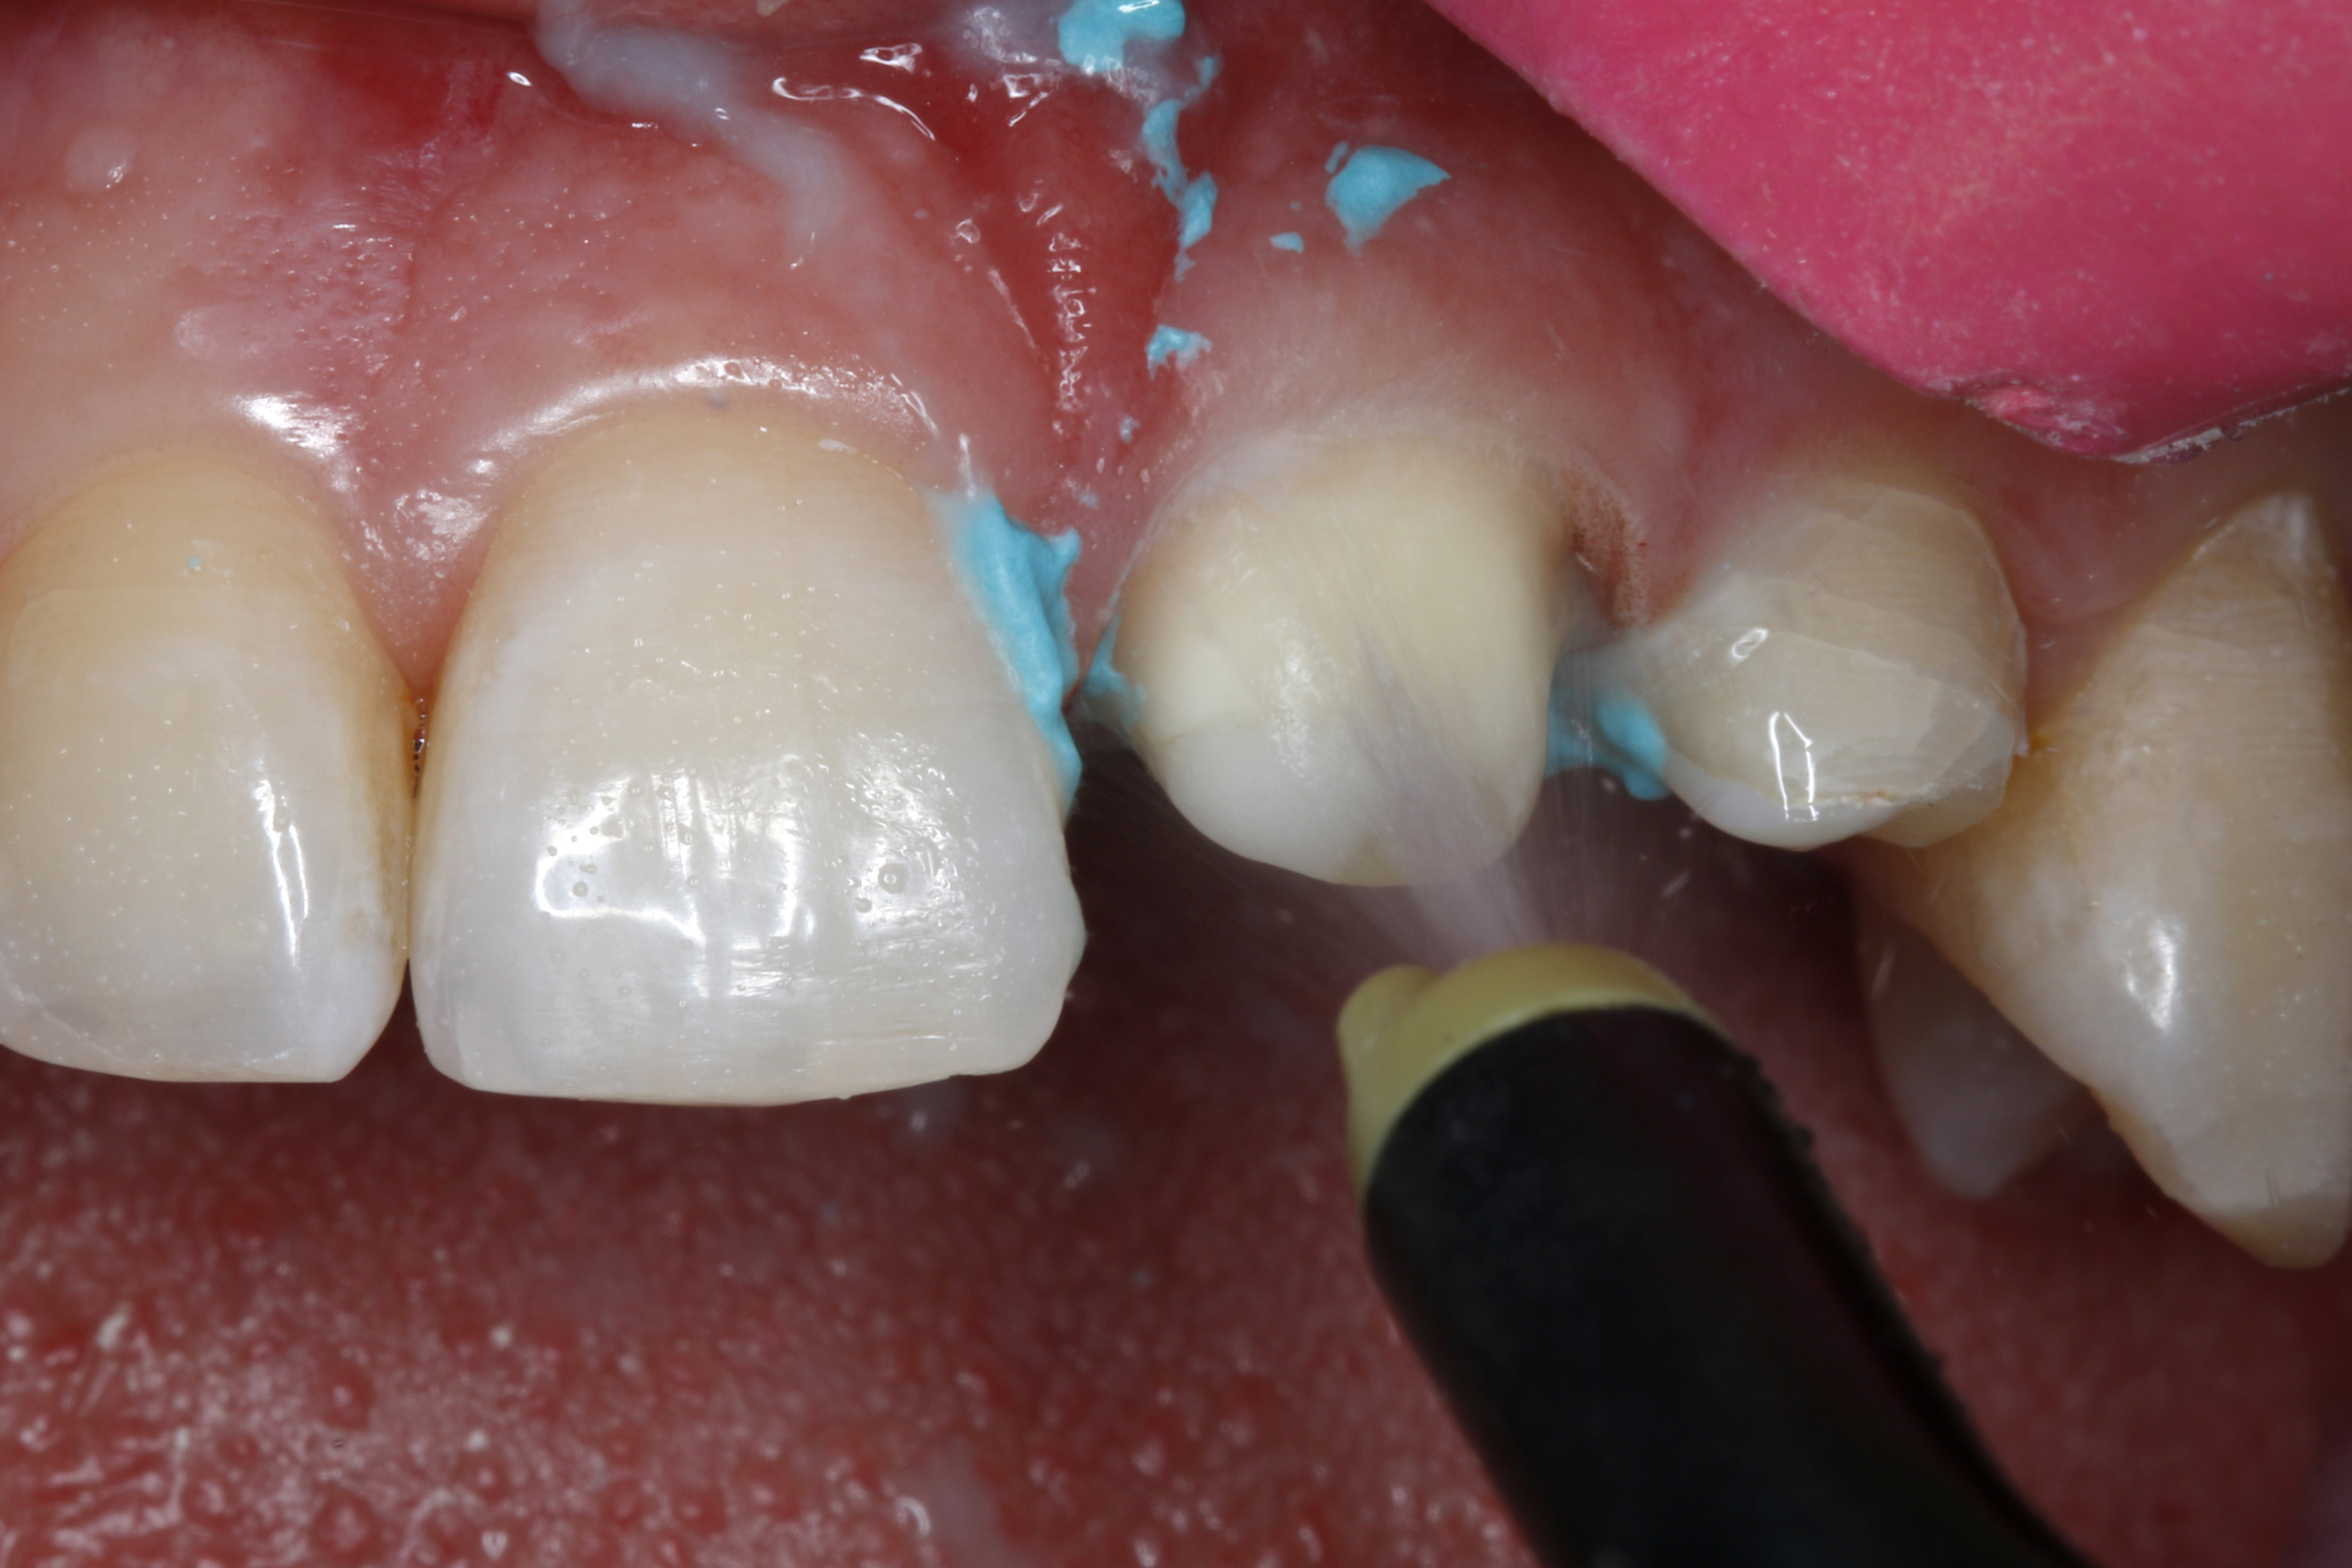

Ryc. 8. Po upływie od 1 do 2 minut ostrożnie wypłukuje się pastę retrakcyjną strumieniem wody i sprężonego powietrza stosując ssak, a następnie osusza powietrzem niezawierającym oleju.

Ryc. 9. Możliwe było optymalne przygotowanie zęba 21 do pobrania wycisku, z zapewnieniem dobrej widoczności na całym obwodzie bruzdy dziąsłowej. Przy pomocy pasty retrakcyjnej wyraźnie odsłonięto brzeg preparacji, otwierając go i zapewniając suchość.